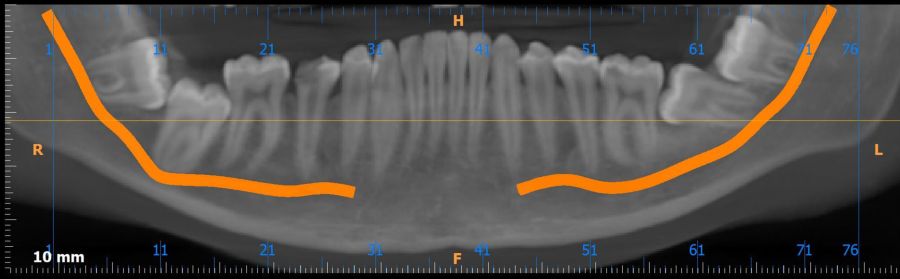

Métodos: Se presenta el caso clínico de un paciente varón de 18 años en el que, tras la realización de una CBCT de la arcada mandibular, se observó la retención de los segundos molares mandibulares permanentes junto con los terceros molares mandibulares.

Conclusiones: La retención del segundo molar mandibular es un hallazgo creciente en jóvenes y requiere un diagnóstico precoz para evitar complicaciones, siendo la CBCT la herramienta diagnóstica más precisa para evaluar la posición y riesgos asociados. Las opciones terapéuticas son diversas y siempre deben individualizarse según la anatomía, el pronóstico y las características del paciente.

Methods: We present the case of an 18-year-old male patient in whom, after performing a CBCT of the mandibular arch, retention of the permanent mandibular second molars was observed, along with the mandibular third molars.

Conclusions: Retention of the mandibular second molar is becoming more common in young patients and needs to be diagnosed early to avoid complications. CBCT is the most accurate tool to assess the tooth position and possible risks. Treatment options vary, and they should always be based on the patient’s anatomy, prognosis, and individual characteristics.